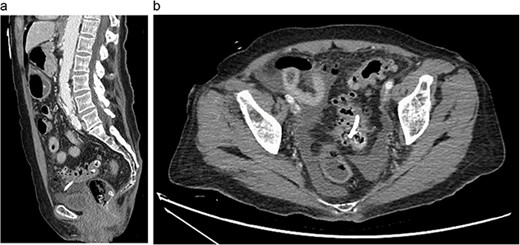

Eleven days later, the patient presented to the emergency department with abdominal pain. During transit to the hospital, she exhibited mild hypotension with a systolic blood pressure in the 90s and was given 500 cc of intravenous normal saline. Upon arrival, her vital signs had stabilized with a temperature of 36.4°C, blood pressure of 122/63 mmHg, heart rate of 81 bpm and oxygen saturation of 94% on room air. Physical examination revealed a moderately distended, rigid abdomen with diffuse tenderness and involuntary guarding. Biochemical investigations demonstrated a leukocyte count of 4.2 x 109 K/µL and a lactate of 3.2 mmol/L. Liver function tests, coagulation profile and electrolytes were unremarkable. Computed tomography (CT) imaging of the abdomen and pelvis with intravenous contrast demonstrated free fluid in the peritoneal cavity with moderate scattered pneumoperitoneum and migrated biliary stent that extended from the sigmoid colon into the peritoneal cavity (Fig. 2).

Abdominal CT showing migrated biliary stent that perforates the sigmoid colon in the sagittal (a) and axial (b) views. Pneumoperitoneum and free fluid in the pelvis are also noted.